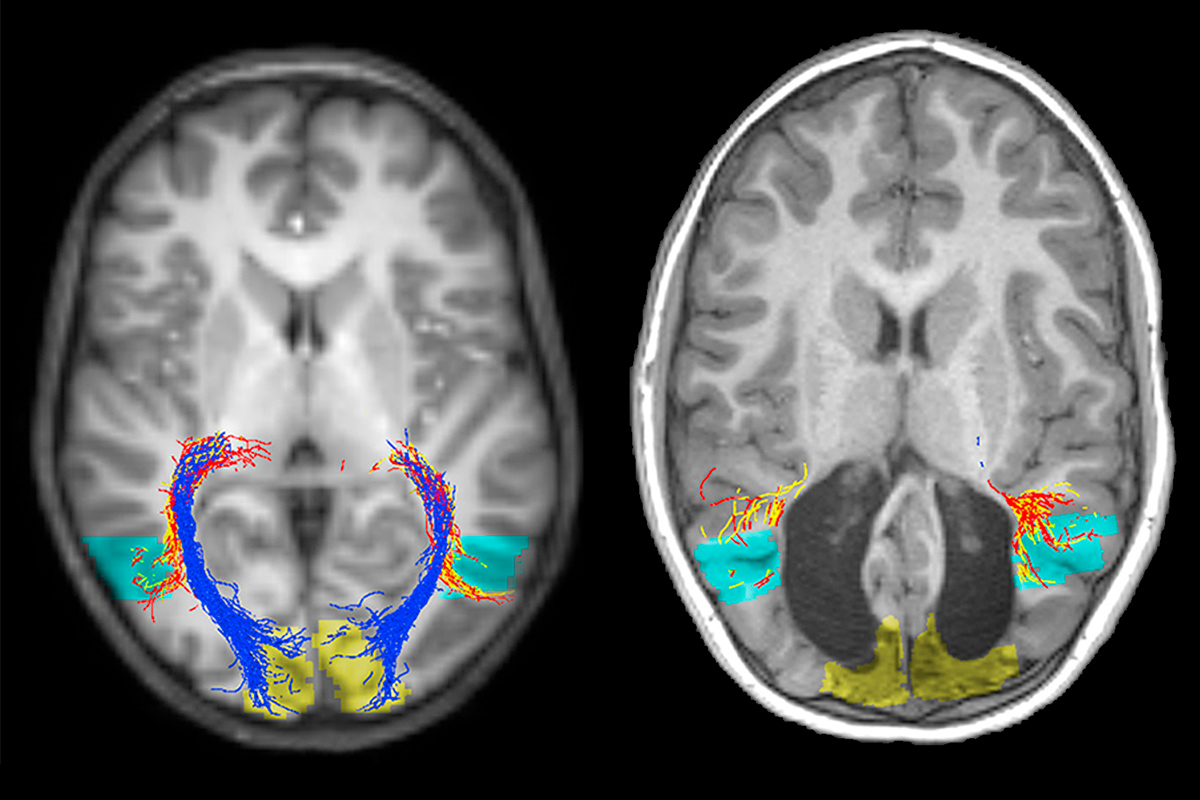

The case of a 7-year-old Australian boy who was supposed to lose sight at two weeks old but can still see has stunned scientists.